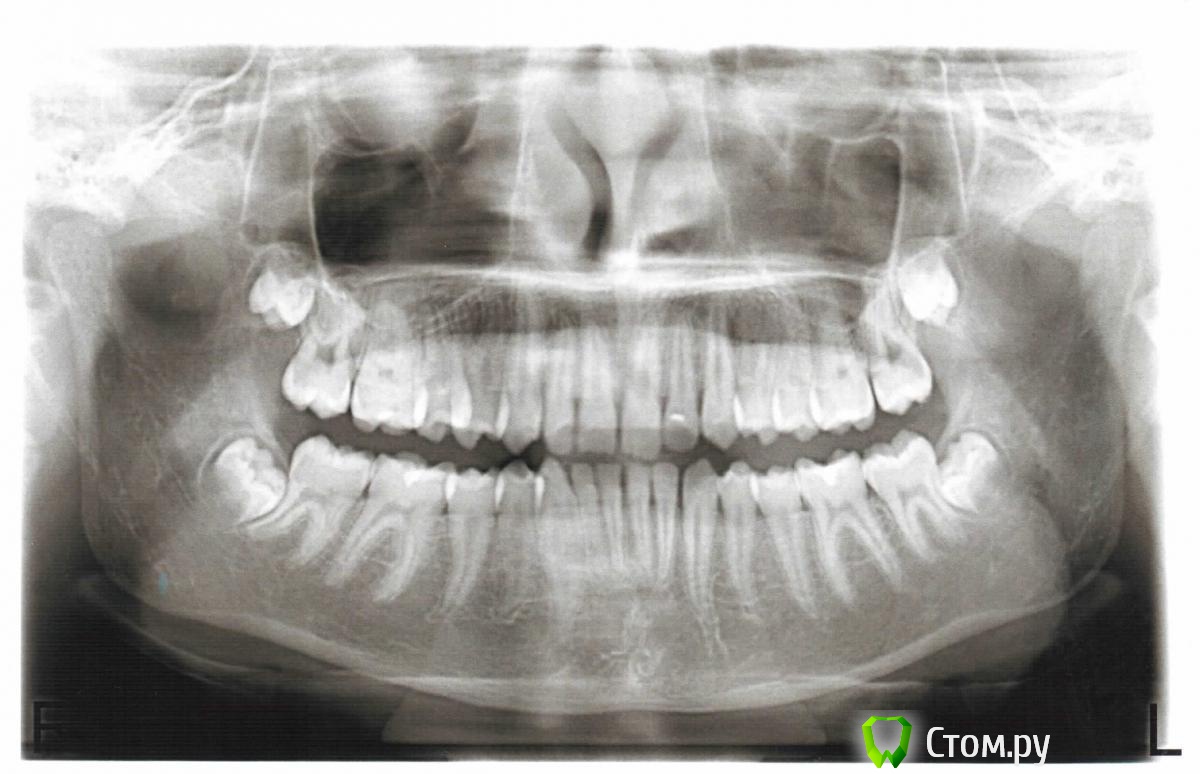

Force Опубликовано 16 января, 2014 Поделиться Опубликовано 16 января, 2014 Нижняя челюсть в ретропозиции, нижняя микрогнатия. Дефицит места для прорезывания зубов мудрости. Избыточный наклон нижних зубов. Двойная окклюзионная плоскость. Это все показания для удаления нижних зубов мудрости. Доктора лучше поставить в известность, но думаю она и сама рада будет. Верхние восьмерки не критичны для дистального прикуса, и расположены они весьма высоко - не достать без серьезного вреда. А нижние - близко и без корней- заживет быстро, если хирург опытный 1 Ссылка на комментарий

vera_nika Опубликовано 27 января, 2014 Автор Поделиться Опубликовано 27 января, 2014 (изменено) Можно я в этой темке продолжу? Надеюсь, кто-нибудь ответит (возможно, Force? ). Всем высказавшим своё мнение будем очень благодарны!!!Сегодня были на очередном приеме у лечащего. После разговора с ней хочется плакать от отчаяния. Постараюсь кратко, но наиболее точно изложить его суть.Я: Поставим ли мы в след.месяце форсус?Она: Форсус ставить рано. Носите тяги. Форсус - очень жесткий аппарат, что очень плохо для сустава. Ему с этим суставом всю жизнь жить. Скорее всего вообще обойдемся тягами, они мягко( ) выдвинут его челюсть вперед.Я: Но, насколько я знаю, сейчас нужно наиболее жесткий аппарат использовать. (На форуме я читала, что нельзя ссылаться на мнение врачей с Вашего форума, по моему об этом Skip писал). Тяги постоянно он не носит!!!Она: Воздействуйте на него.Я: Я настаиваю на Форсусе.Она: У него челюсть нижняя слишком маленькая, очень большая саггитальная щель, форсус тут не поможет, сначала будем расширять челюсть, для этого я вставила между зубами (клыком и премоляром?) пружины. Мальчик ещё растёт, поэтому и челюсть должна вырасти. Вообще самое лучшее в вашей ситуации - удаление двух верхних премоляров, чтоб сравнять размер челюстей.Я: Это не обсуждается, я категорически против. Лучше сделаем операцию после 18 лет. Сколько ещё будем носить тяги?Она: Ну, дело Ваше. Насчет тяг - не знаю. Посмотрим.Я: Нам нужно удалить две нижние восьмерки.Она: Зачем?Я: (Описываю как помню диагнозы-показания Force)Она: Ничего удалять не нужно. Мы будем расширять челюсть, места им хватит. В крайнем случае всегда их удалить успеем.Никогда за последнее время так ужасно себя не чувствовала, как после этого разговора - тоска и безысходность. Неужели никакой аппарат нам уже не поможет? Пишу это и плачу, чесс слово...Помогите, пожалуйста, ответьте на вопросы:1) можно ли этими пружинами расширить челюсть? они же вроде только зубы друг от друга отталкивают, хуже не будет? и вообще реально в нашем возрасте её расширить?2) выложила фото, на которых видно, на сколько не смыкаются его задние зубы, т.е. какая большая щель между ними, если он ставит челюсть в правильное положение. Это и есть причина, из-за которой форсус ставить нельзя? Я то, дура, надеялась, что всё само собой нормализуется после установки аппарата. (Раньше в таком ракурсе фото выложить ума не хватило).3) смущает, что центр сместился на передних зубах (может из-за накусочной площадки на верхних единицах, потому что когда мальчик ставил на неё зубы, говорил, что ровно поставить не может, ему площадка мешает). Но это наверно выровняется брекетами? т.к. площадку она сегодня убрала.4) насколько оправдана такая тактика лечения? поймите, я не то чтоб ей не доверяю. Просто смущает обстоятельство, что она ничего никогда конкретно не говорит, всё время "посмотрим". Даже перед началом лечения (на форуме не раз читала, что врач должен обсуждать план лечения с пациентом) НИЧЕГО не было разъяснено. На мою просьбу в общих чертах объяснить, что и как будет, она сказала: "Ну и как я Вам это покажу и объясню?" Я говорю, да хоть на модельках челюстей. Она ответила в том духе, что не морочьте голову ни себе ни мне, всё будет видно в процессе лечения. Получается, ясной картины у неё и тогда не было и сейчас нет. Или может это в порядке вещей? Я понимаю, что ортодонтия - область ОЧЕНЬ сложная.В общем и целом, на данный момент мною решено всё же удалить две нижние восьмерки, как советовал Force, не дожидаясь её согласия и не надеясь на расширение челюсти (может я не права?)5) И МОЖНО ЛИ МАЛЬЧИКУ ВСЁ ЖЕ ПОСТАВИТЬ АППАРАТ ДЛЯ ВЫДВИЖЕНИЯ ЧЕЛЮСТИ? (Учитывая свежевыложенные снимки).Напишите, пожалуйста, если нужны ещё какие-то фото. Если дистанционно трудно что-то посоветовать, может хоть врача хорошего, опытного порекомендуете в Казани. Я понимаю, что долечивать и перелечивать не возьмутся, но хоть посоветуют что-то, а то так и буду бить себя ушами по щекам от отчаяния...Пожалуйста, не оставьте мой пост без внимания! Одна надежда на вас, уважаемые ортодонты и другие специалисты!!! Изменено 27 января, 2014 пользователем vera_nika Ссылка на комментарий